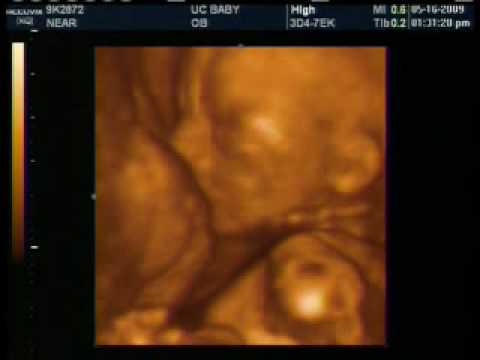

UCBABY Visit Clip 1 - YouTube

Out visit to UCBABY in Cambridge, On clip 1. Skip navigation Upload. Sign in. Search. Loading Close. Yeah, keep it Undo Close. This video is unavailable. Watch Queue My First Peekaboo 3D Ultrasound Video - Duration: 1:04. MyFirstPeekabooUS 15,949 views. 1:04 3D Ultrasound ... View Video